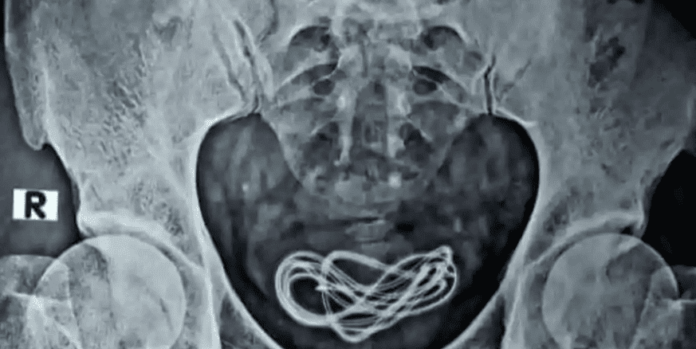

Proses X-Ray dilakukan untuk melihat apakah ada sesuatu di perut. Proses operasi dilakukan tapi mereka tidak menemukan benda yang dicari di saluran pencernaan.

Oleh karena itu, dokter mengambil inisiatif untuk melakukan X-Ray tambahan di ruang operasi dan menemukan bahwa ada sebuah kabel pengisian daya, dan bukan earphone yang sebelumnya diklaim oleh pasien.

Kesimpulan ini diambil karena para dokter telah menemukan kabel pengisian daya bersarang di dalam kandung kemih yang terhubung ke uretra.